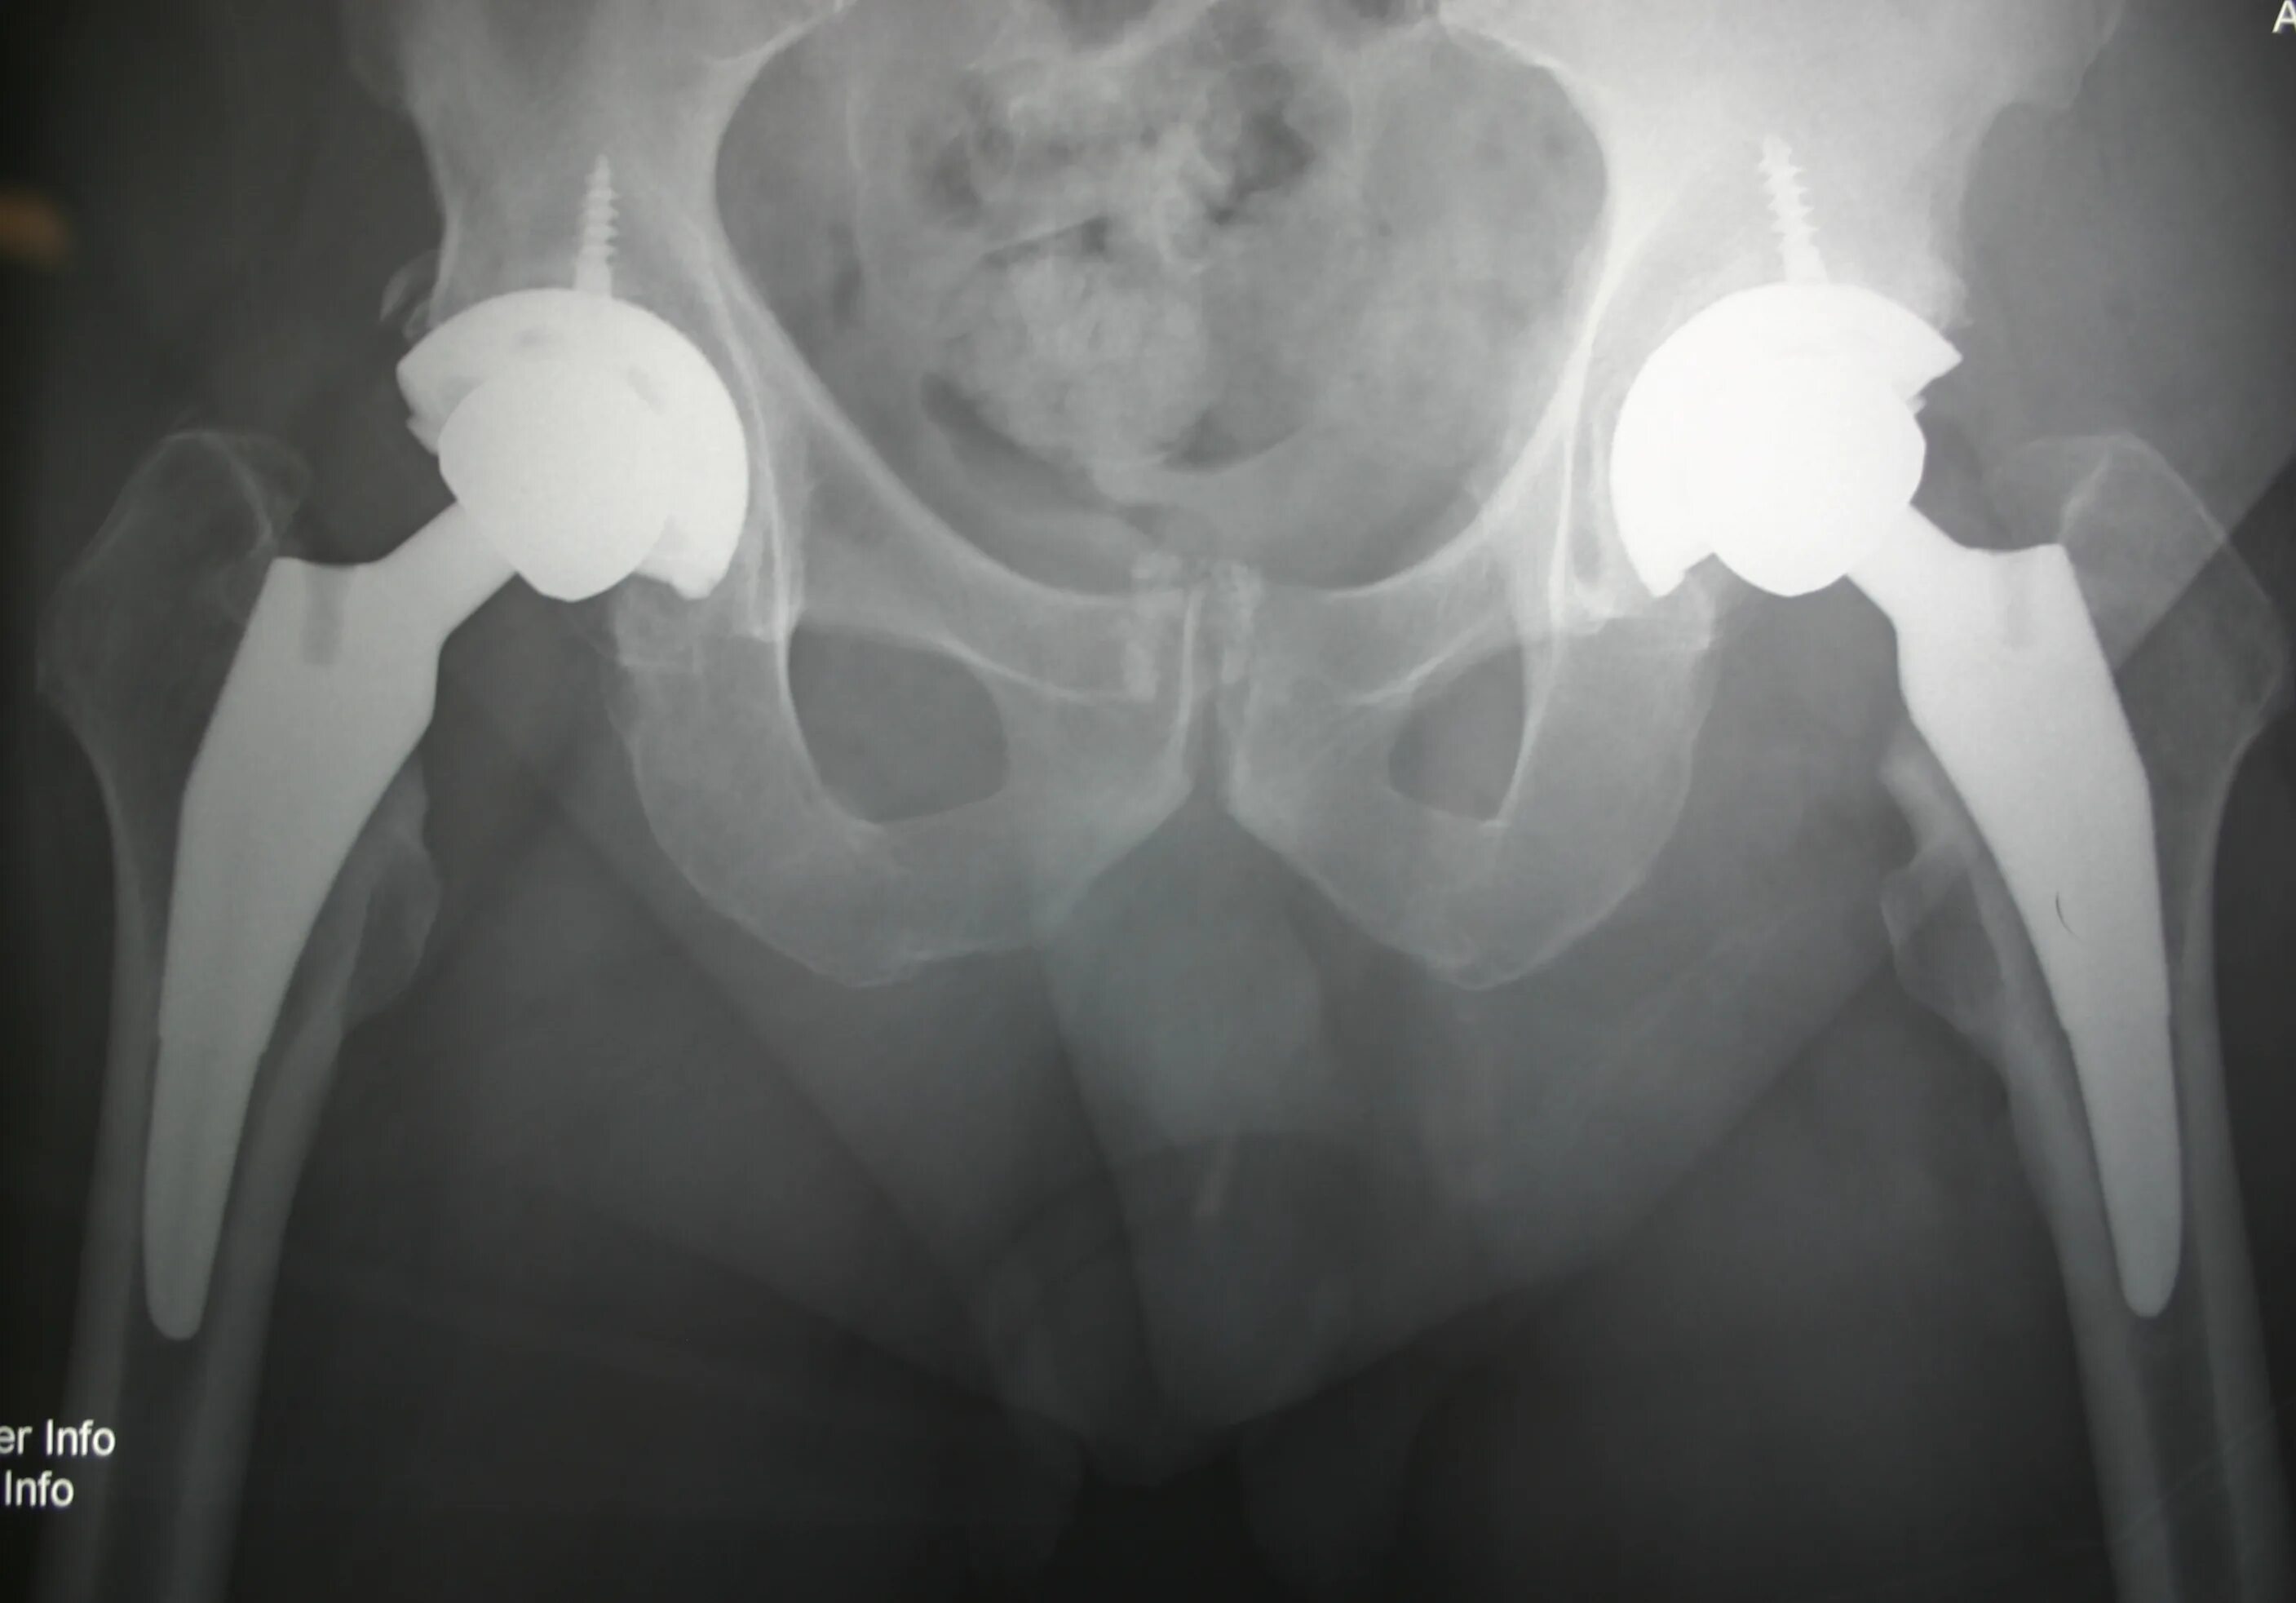

Стерся тазобедренных суставов